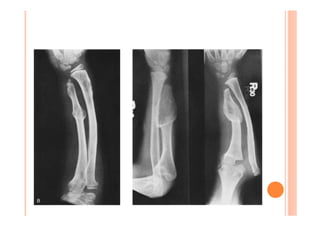

MADELUNG – X RAYS

Excess palmar and radial

MADELUNG – XRAYS Excess palmar and radial angulation Ulna Plus